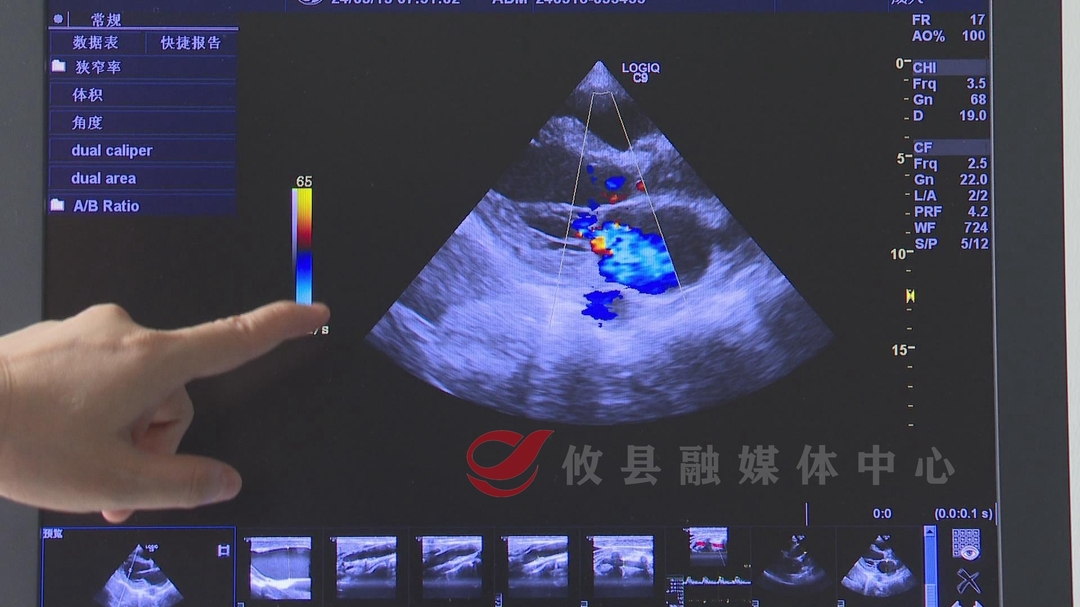

就这样,攸县第三人民医院的超声检测设备不断升级,由一台开展腹部及普通产科超声检查的手提式黑白机,升级成了可以进行心脏、四肢血管、颈部血管、浅表小器官以及胎儿的孕早期超声检查的设备,后面还陆续引进了中晚期系统筛查,腔道超声等新技术新项目。有一次,一个腹部疼痛的病人来就医,当时谭慧敏在检查患者的肝胆胰脾部位后并没有发现问题,但患者依然疼痛难忍,谭慧敏想到了是不是血管方面的问题。于是她用探头扫查了患者腹部的大血管腹主动脉有没有夹层,结果在胰腺的后方,果然发现了肠系膜上动脉里面有个夹层,见此情景,她立马建议患者到上级医院诊治。

攸县第三人民医院超声诊断科主任谭慧敏:“他在省人民医院进一步检查以后,发现跟我们的诊断是一致的,患者也得到了及时的治疗。通过这个事情,我们感受在平常的工作中,我们也要仔细严谨,全方位的考虑病情,去分析病情,不能放过一点一滴蛛丝马迹,做好病人的‘一双眼睛’。”